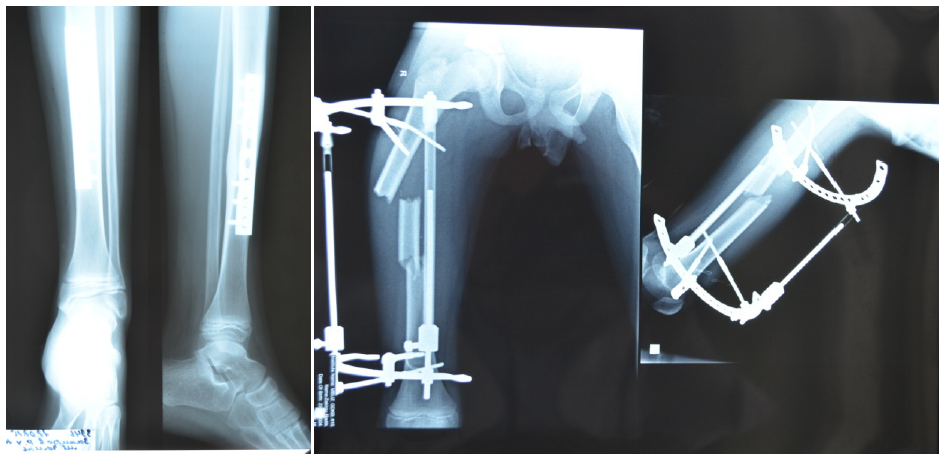

Здоровье на первом месте: диагностика и лечение через рентгеноскопию конечностей

Раздел: Снимки-откровения